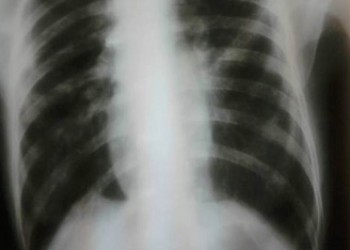

La nou-născut, silueta cardiacă reprezintă circa 1/3 din lățimea toracelui. Ce facem când vedem o radiografie cum este cea din imagine la un adult?

Nu este vorba despre o malformație, ci despre un cord tubular, cel mai adesea în cadrul unei patologii pleuro-pulmonare. Acest aspect apare atunci când diametrul maxim orizontal al cordului este sub 11 cm sau indicele cardio-toracic (raportul dintre diametrul cardiac transvers maxim şi diametrul toracic transvers maxim) este sub 1/3.

Cordul tubular poate fi întâlnit în BPOC cu emfizem sever, astm bronșic, alte sindroame de hiperinflație pulmonară, pneumotorax bilateral sau obstrucție de bronhii principale (cu colabarea plămânului în hil) și în unele cauze de insuficiență adrenală (boala Addison), datorită hipovolemiei cronice și încărcării volemice scăzute a aparatului cardiocirculator.

În cazul bolilor pulmonare obstructive, consecința acestei “înghesuiri” a cordului de către plămânul hiperinflat este umplerea deficitară a ventriculului stâng, disfuncție diastolică și debit cardiac scăzut.